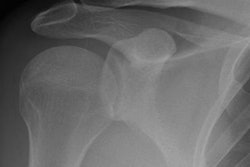

22 abril 2019 -- Historia: Un hombre de unos 70 años acude por sudoración nocturna observada en el último mes. No tiene fiebre ni antecedentes de enfermedades anteriores. En el análisis sanguíneo se observa una elevación de la velocidad de sedimentación, la proteína C reactiva y la fosfatasa alcalina.

Se deriva al paciente para la realización de una TC de tórax y abdomen. A continuación se muestran imágenes de la TC axial. Haga clic para ampliar.